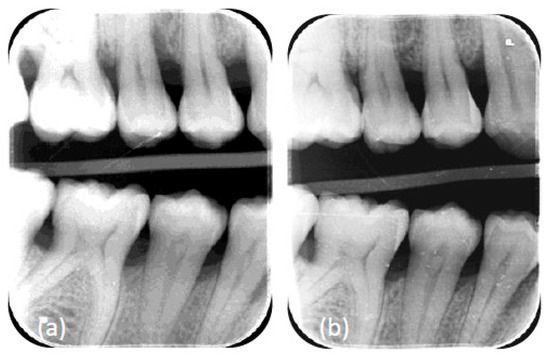

2.3. Surgical Phase